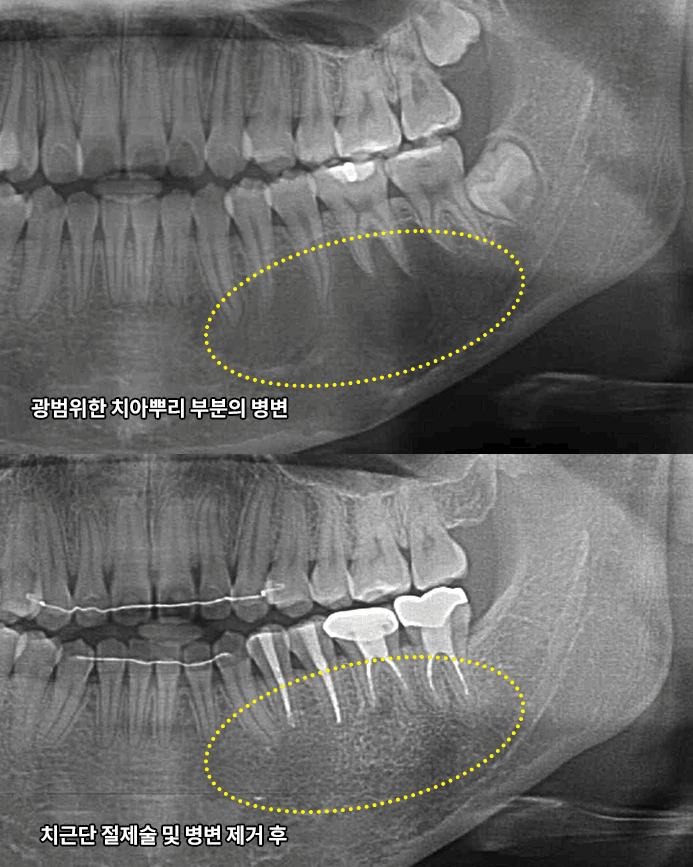

신경치료는 충치가 신경까지 번진 경우, 치아가 부러져 신경이 노출된 경우, 뿌리에 염증이 생긴 경우 진행하는 치료방법입니다. 신경관이 막혀있거나 신경관에 post가 박혀있는 경우 치료의 난이도는 매우 어려워 지며 많은 분들이 발치를 권유 받습니다. 청담뷰치과는 자연치아살리기 진료를 전문적으로 다뤄왔기에 막힌 신경관을 찾거나 만곡이 심한 신경관을 다루는 치료까지 성공적인 결과를 제공해 드릴 수 있습니다.